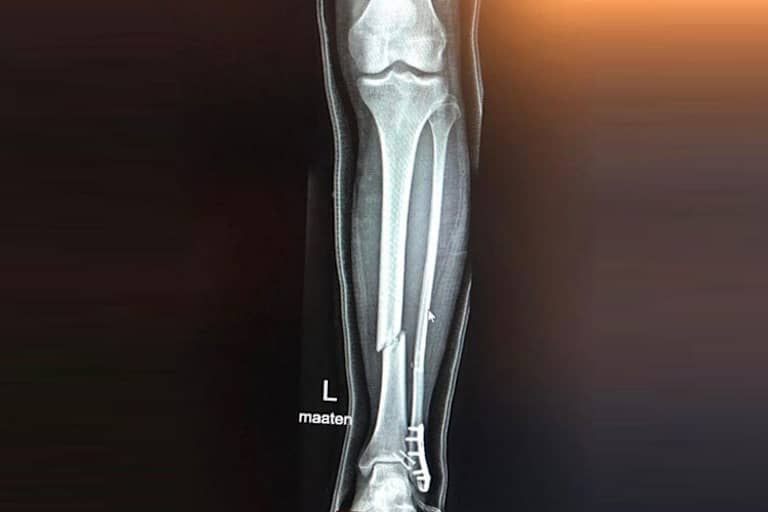

Mika Kallio: Schien- und Wadenbein gebrochen

Der finnische Red Bull-KTM-Testfahrer Mika Kallio hat gemeinsam mit Stefan Bradl und Michele Pirro sowie seinem KTM-Kollegen Dani Pedrosa am 16./17. Februar noch auf dem Circuito de Jerez die neue KTM RC16 getestet. Jetzt hat er sich in seiner Heimat beim Motorrad-Training auf Eis am linken Bein einen Schien- und Wadenbeinbruch zugezogen – noch dazu ohne richtigen Sturz.

"Jetzt warte ich auf die Operation, Schien- und Wadenbein müssen fixiert werden", meldete der 38-jährige Kallio auf Facebook. "Leider hat manchmal ein eigentlich harmloser Fahrfehler schmerzhafte Konsequenzen. Das ist nicht das, was ich für das heutige ‘Ice Road Race‘ im Sinn hatte..." Der 125-ccm-Vizeweltmeister von 2005 (auf KTM) und Moto2-Vizeweltmeister von 2014 (auf Kalex) rechnet mit einer Pause von sieben bis acht Wochen. "Ich möchte mich bei allen entschuldigen, die durch diese Verletzung betroffen sind. Das ist die dunkle Seite des Rennsports. Sogar bei einer Hobby-Fahrt kann es gefährlich werden", schrieb Mika.

Red Bull-KTM-Teambesitzer Aki Ajo war bei diesem Event als Zuschauer dabei. "Ich habe Mika zum Ambulanzfahrzeug begleitet", schilderte er im Gespräch mit SPEEDWEEK.com. "Es war beim Finischen Meisterschaftslauf in Seinäjoki und ist im ersten Vorlauf zum 250-ccm-Finale passiert. Mika machte einen kleinen Fehler, er konnte einen Sturz vemeiden, aber dann hatte er nicht genug Auslaufzone, deshalb musste er über eine Schneemauer fahren. Er hat sein linkes Bein dann beim Aufprall an der Schneemauer demoliert."